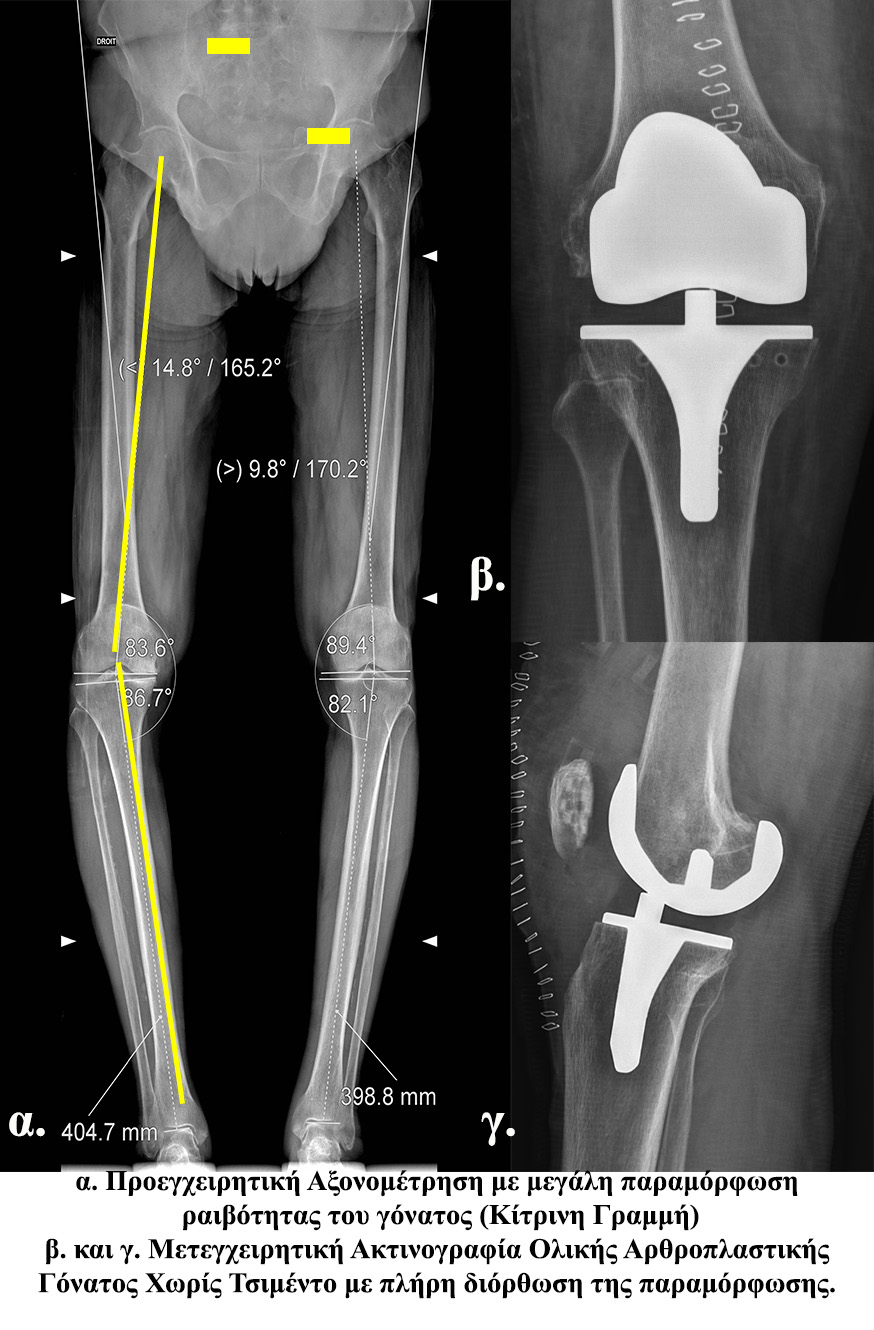

- - Η ολική αρθροπλαστική του γόνατος αποτελεί εμφυτεύσιμο ορθοπαιδικό υλικό το οποίο αντικαθιστά εξ’ ολοκλήρου την άρθρωση του γόνατος.

- - Η σταθεροποίηση της μπορεί να πραγματοποιηθεί με 2 μεθόδους:

- - Με τη χρήση “βιολογικού” – ακρυλικού τσιμέντου (cemented)

- - Χωρίς τη χρήση αυτού (cementless). Στην περίπτωση αυτή τα τμήματα της αρθροπλαστικής καλύπτονται από μια επίστρωση υδροξυαπατίτη (συστατικό του φυσιολογικού οστού).